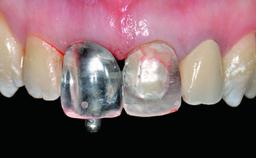

Replacement of a Failing Upper Left Central Incisor: Immediate Placement of an RC Bone Level Implant and Provisionalization

Abutment Type CAD/CAM

Prosthesis Type FDP

Retention Cemented, with prosthesis margin < 3mm submucosal Cemented, with prosthesis margin < 3mm submucosal